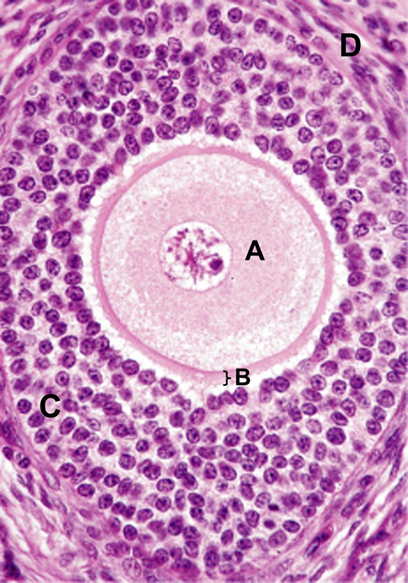

Which cell type shown would have the most abundant receptors for luteinizing hormone (LH)?

A. A

B. B

C. C

D. D

E. E

B.

In the image below, which part of the follicle produces estrogen?

A. A

B. B

C. C

D. D

C. C

In the image below, which part of the follicle contains cells that are directly stimulated by LH?

A. A

B. B

C. C

D. D

D. D

In the image below, identify the part of the follicle that produces estrogen.

A. A

B. B

C. C

D. D

C. C